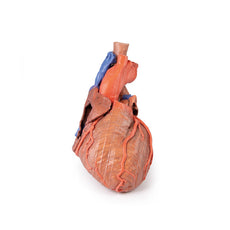

3D Printed Heart internal structures Replica

The anterior wall of the right ventricle has also been removed to expose the right atrioventricular valve and its three cusps (anterior, posterior, and septal), including the chordae tendineae connecting them to respective papillary muscles projecting from trabeculae carneae (including a septomarginal trabecula entering the anterior papillary muscle from the interventricular septum). The smooth wall of the conus arteriosus is also exposed leading to the pulmonary semilunar valve (left, right, and anterior cusps) at the base of the pulmonary trunk. Preserved and encircling the right atrioventricular valve is the right coronary artery, ultimately passing to the posterior aspect and the origin of the posterior interventricular artery and atrioventricular nodal artery.

On the posterior side of heart the terminations of the pulmonary veins are visible entering the opened left atrium. Just anterior to the depression of the fossa ovalis in the interatrial septum the left atrioventricular valve with its two cusps (anterior and posterior) is preserved, along with the associated chordae tendineae and papillary muscles in the ventricle.

The walls of the opened left ventricle preserve well-developed trabeculae carneae. At the apex of the ventricle the aortic semilunar valve (with left, right, and posterior cusps preserved) can be seen at the base of the sectioned aorta alongside the origin of both coronary arteries. The left coronary artery in this specimen is very short, giving rise almost immediately from its origin to the left anterior descending artery, the diagonal artery, the ramus intermedius, and the circumflex branch. The latter branch passes between the left atrium and ventricle adjacent to the opened coronary sinus leading to the right atrium. The left anterior descending branch penetrates the myocardium in this individual and travels through the tissue, only emerging superficially to become visible again near the apex.

3D Printed Heart internal structures replica

This 3D printed heart has been dissected to display the internal structures of the chambers. At the base of the heart the termination of the superior vena cava is preserved entering the right atrium. Part of the inferior vena cava is also preserved on the inferior aspect of the right atrium; however, most of the vessel lumen and much of the anterior wall has been removed to expose the pectinate muscles of the right auricle and the fossa ovalis (which is nearly translucent in the 3D print).The anterior wall of the right ventricle has also been removed to expose the right atrioventricular valve and its three cusps (anterior, posterior, and septal), including the chordae tendineae connecting them to respective papillary muscles projecting from trabeculae carneae (including a septomarginal trabecula entering the anterior papillary muscle from the interventricular septum). The smooth wall of the conus arteriosus is also exposed leading to the pulmonary semilunar valve (left, right, and anterior cusps) at the base of the pulmonary trunk. Preserved and encircling the right atrioventricular valve is the right coronary artery, ultimately passing to the posterior aspect and the origin of the posterior interventricular artery and atrioventricular nodal artery.

On the posterior side of heart the terminations of the pulmonary veins are visible entering the opened left atrium. Just anterior to the depression of the fossa ovalis in the interatrial septum the left atrioventricular valve with its two cusps (anterior and posterior) is preserved, along with the associated chordae tendineae and papillary muscles in the ventricle.

The walls of the opened left ventricle preserve well-developed trabeculae carneae. At the apex of the ventricle the aortic semilunar valve (with left, right, and posterior cusps preserved) can be seen at the base of the sectioned aorta alongside the origin of both coronary arteries. The left coronary artery in this specimen is very short, giving rise almost immediately from its origin to the left anterior descending artery, the diagonal artery, the ramus intermedius, and the circumflex branch. The latter branch passes between the left atrium and ventricle adjacent to the opened coronary sinus leading to the right atrium. The left anterior descending branch penetrates the myocardium in this individual and travels through the tissue, only emerging superficially to become visible again near the apex.